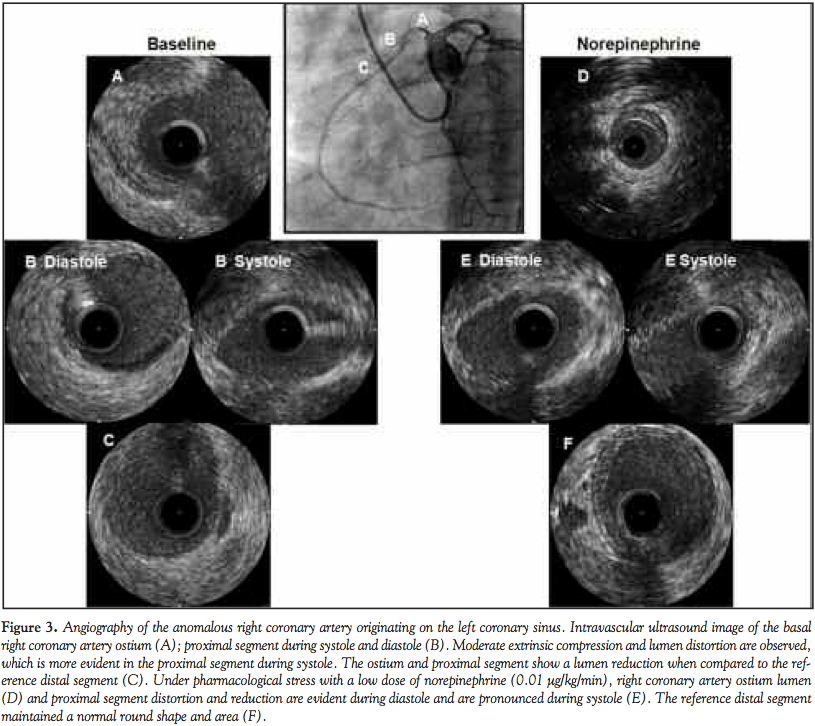

Case Report 3. The third patient was a 50-year-old male who was previously asymptomatic but required treatment after presenting syncope during physical effort. After regaining consciousness, the patient complained of chest pain, which was relieved by sublingual nitrate. The electrocardiogram and physical examination in the emergency room were normal, except for high blood pressure, although cardiac enzymes were elevated. A coronary angiography revealed the dominant origin of the RCA from the left sinus of Valsalva and coursing between the aorta and pulmonary trunk.

There was a mild constriction of the RCA (Figure 3). The left coronary artery was normal, and there was no significant atherosclerosis by coronary angiography. Coronary angiography showed extrinsic compression of the proximal segment of the RCA.

The patient underwent IVUS, which showed extrinsic compression of the proximal segment of the RCA by the aorta and pulmonary trunk. The minimal luminal area was 5.67 mm2. No significant atherosclerosis was observed by IVUS. As the extrinsic compression did not indicate a critical reduction of the lumen area, a pharmacological stress test was performed using norepinephrine. After 3 minutes with a 0.01 μg/kg/min infusion, the patient showed typical angina. The IVUS showed coronary compression with an expressive reduction of the luminal area to 3.14 mm2 (Figure 3). The infusion of norepinephrine was suspended and nitroglycerin was administered; there was an immediate reduction in symptoms.

Discussion. For these 3 patients, the main findings from the IVUS were the absence of significant atherosclerotic disease, a marked reduction in the luminal area at systole, and an asymmetry of the ostium lumen and the proximal segment of the RCA (Table 1). The pharmacological stress test showed a reduction of the coronary lumen that was associated with the development of symptoms.